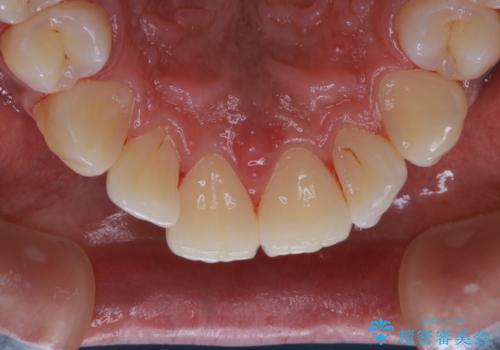

- 電子タバコを吸う習慣があり、ステインがついてしまっている見た目が気になるとのことで来院されました。ステインだけではなく、歯石も全体的に付着していたためPMTC60分コースを行いました。

PMTCは、歯に付着した汚れを除去していくため、着色が気になる場合にも行うことができます。ご自身でのセルフケアだけで着色を落とそうとすると、逆に歯を傷つけてしまったり、精密に汚れを除去できないこともあります。また、日常生活で着色しやすい飲食物を避けたりすることはストレスに感じてしまったり、あまり現実的ではありません。